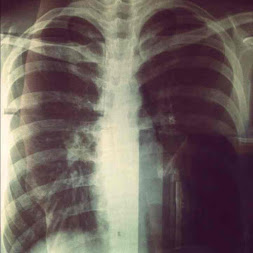

Apparently

my

backbone

arch

to

the

right,

meaning

I'm

no

longer

straight.